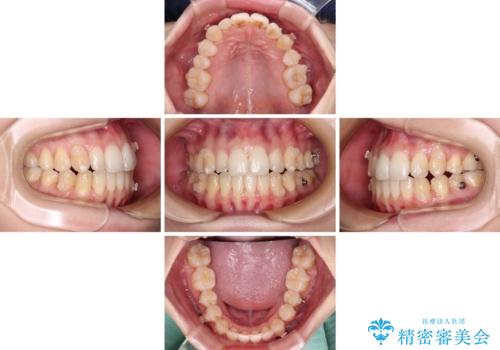

骨格的に下顎が右側に変位していたため、上下正中を合わせることは困難であることは分かっていました。それでも、なるべく合わせるようにとしたため、治療期間は長期間となりました。

長期間とはなりましたが、咬み合わせが改善され、患者様には大変満足していただきました。